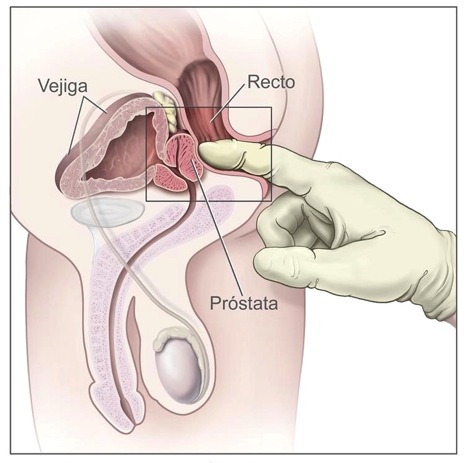

La existencia de cáncer puede sospecharse a partir de diversos síntomas, mediante el examen físico por tacto rectal, un análisis de sangre (PSA) y pruebas de imagen (Ecografía) ; y se confirma tras realizar una biopsia prostática.

Muchos de estos síntomas son idénticos a los de la hipertrofia benigna de próstata, y se debe acudir al urólogo para evaluarlos. En la exploración que realizamos se palpa la próstata con un dedo introducido por el ano (tacto rectal); si existen durezas anormales hacen sospechar un tumor.

Es la única prueba que logra confirmar la existencia del cáncer de próstata. Debe practicarse cuando el tacto rectal y/o el PSA están alterados, y en ocasiones es necesario repetirla.

Se realiza introduciendo una fina aguja hueca a través del recto en el interior de la próstata, para extraer muestras de tejido.